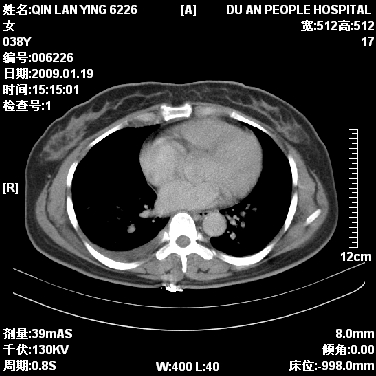

女,38岁,胸疼1个月。wbc:1万4

1)右肺中央型肺癌并右肺上叶阻塞性肺炎、节段性肺不张,纵隔淋巴结转移、右侧胸膜转移、肝脏转移。2)右侧胸腔少量积液。

本病例有几个容易诊断的地方:1、右肺上叶前段支气管闭塞,肺不张。2、淋巴结明显肿大。3、肝脏多个类圆形低密度影呈“牛眼征”改变,高度提示转移。

从影像学角度分析      右肺上叶中央型肺癌,并阻塞性不张、肺炎,纵隔淋巴结、膈顶淋巴结转移。

肝内两个大小不等低密度结节,内可见更低密度影,首先考虑肝内转移瘤,但联想到患者wbc1万4,建议楼主还是做个增强比较明确,除外肝脓肿的可能。